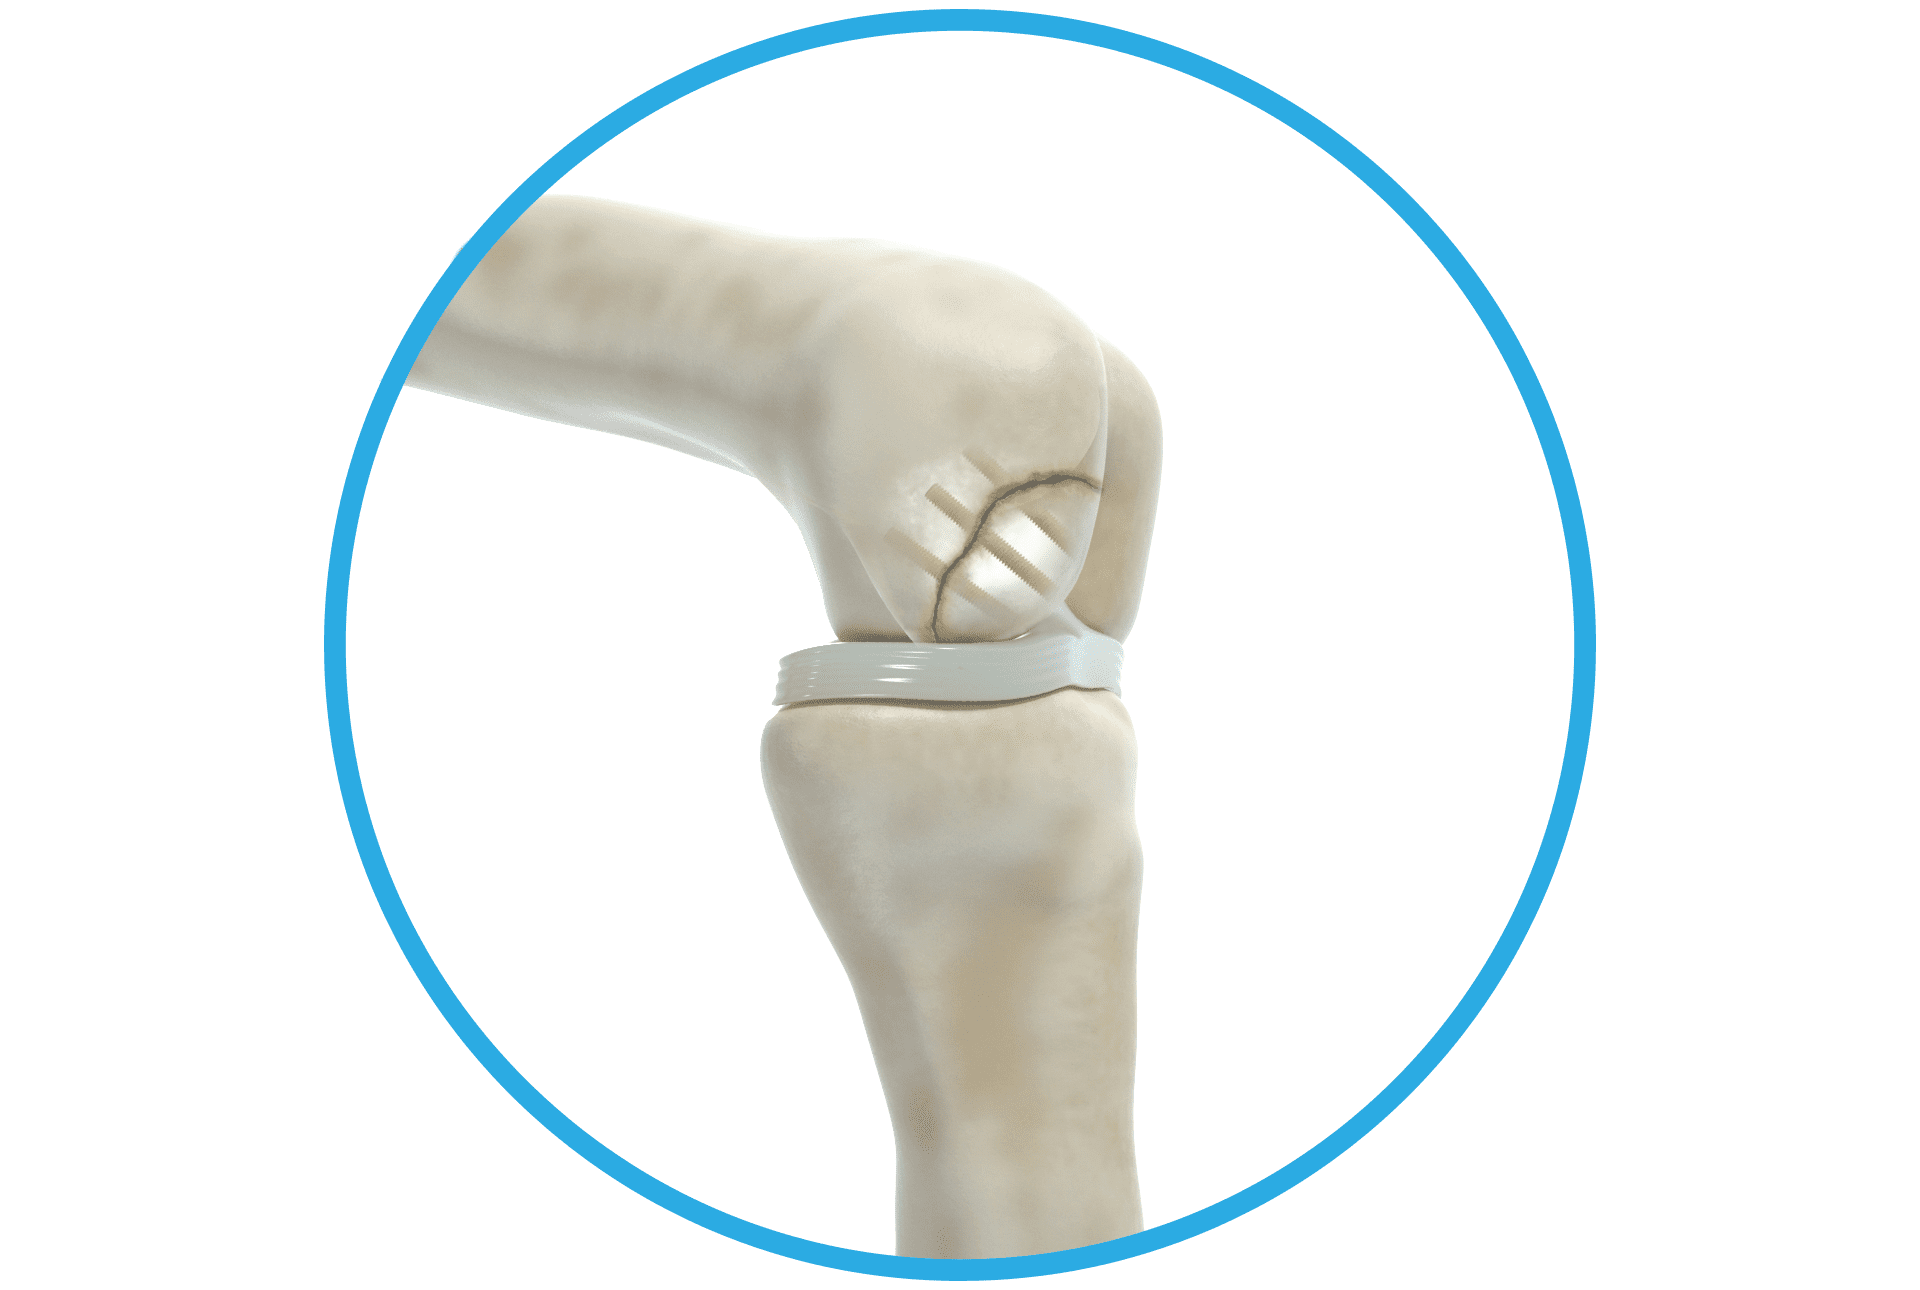

Als Shark Screw® Hero nützen Sie die natürlichen Vorteile intakter Havers-Kanäle und Co-Spaces in der Shark Screw®. Damit setzen Sie eine solide Knochenbrücke mit feinsten Kanälen und Co-Spaces über die und in welche Zellen wandern können. Dadurch wird primäre Knochenheilung zwischen Shark Screw® und Empfängerknochen sowie ein Remodeling der allogenen Knochenschraube möglich.1 Von diesen Eigenschaften profitieren Sie und Ihre Patienten vorzugsweise bei Arthrodesen, Frakturen, Pseudarthrosen und Umstellungen. Einen Auszug aus relevanten Studien zur Shark Screw® finden Sie hier.

Die elektronenmikroskopischen Bilder zeigen die natürliche Struktur der Shark Screw®. Havers-Kanäle bieten dem Empfängerknochen nach Einbringen die Möglichkeit, Anschluss an das Transplantat zu finden. (TU Graz FELMI Prof. DI. Dr. Plank)